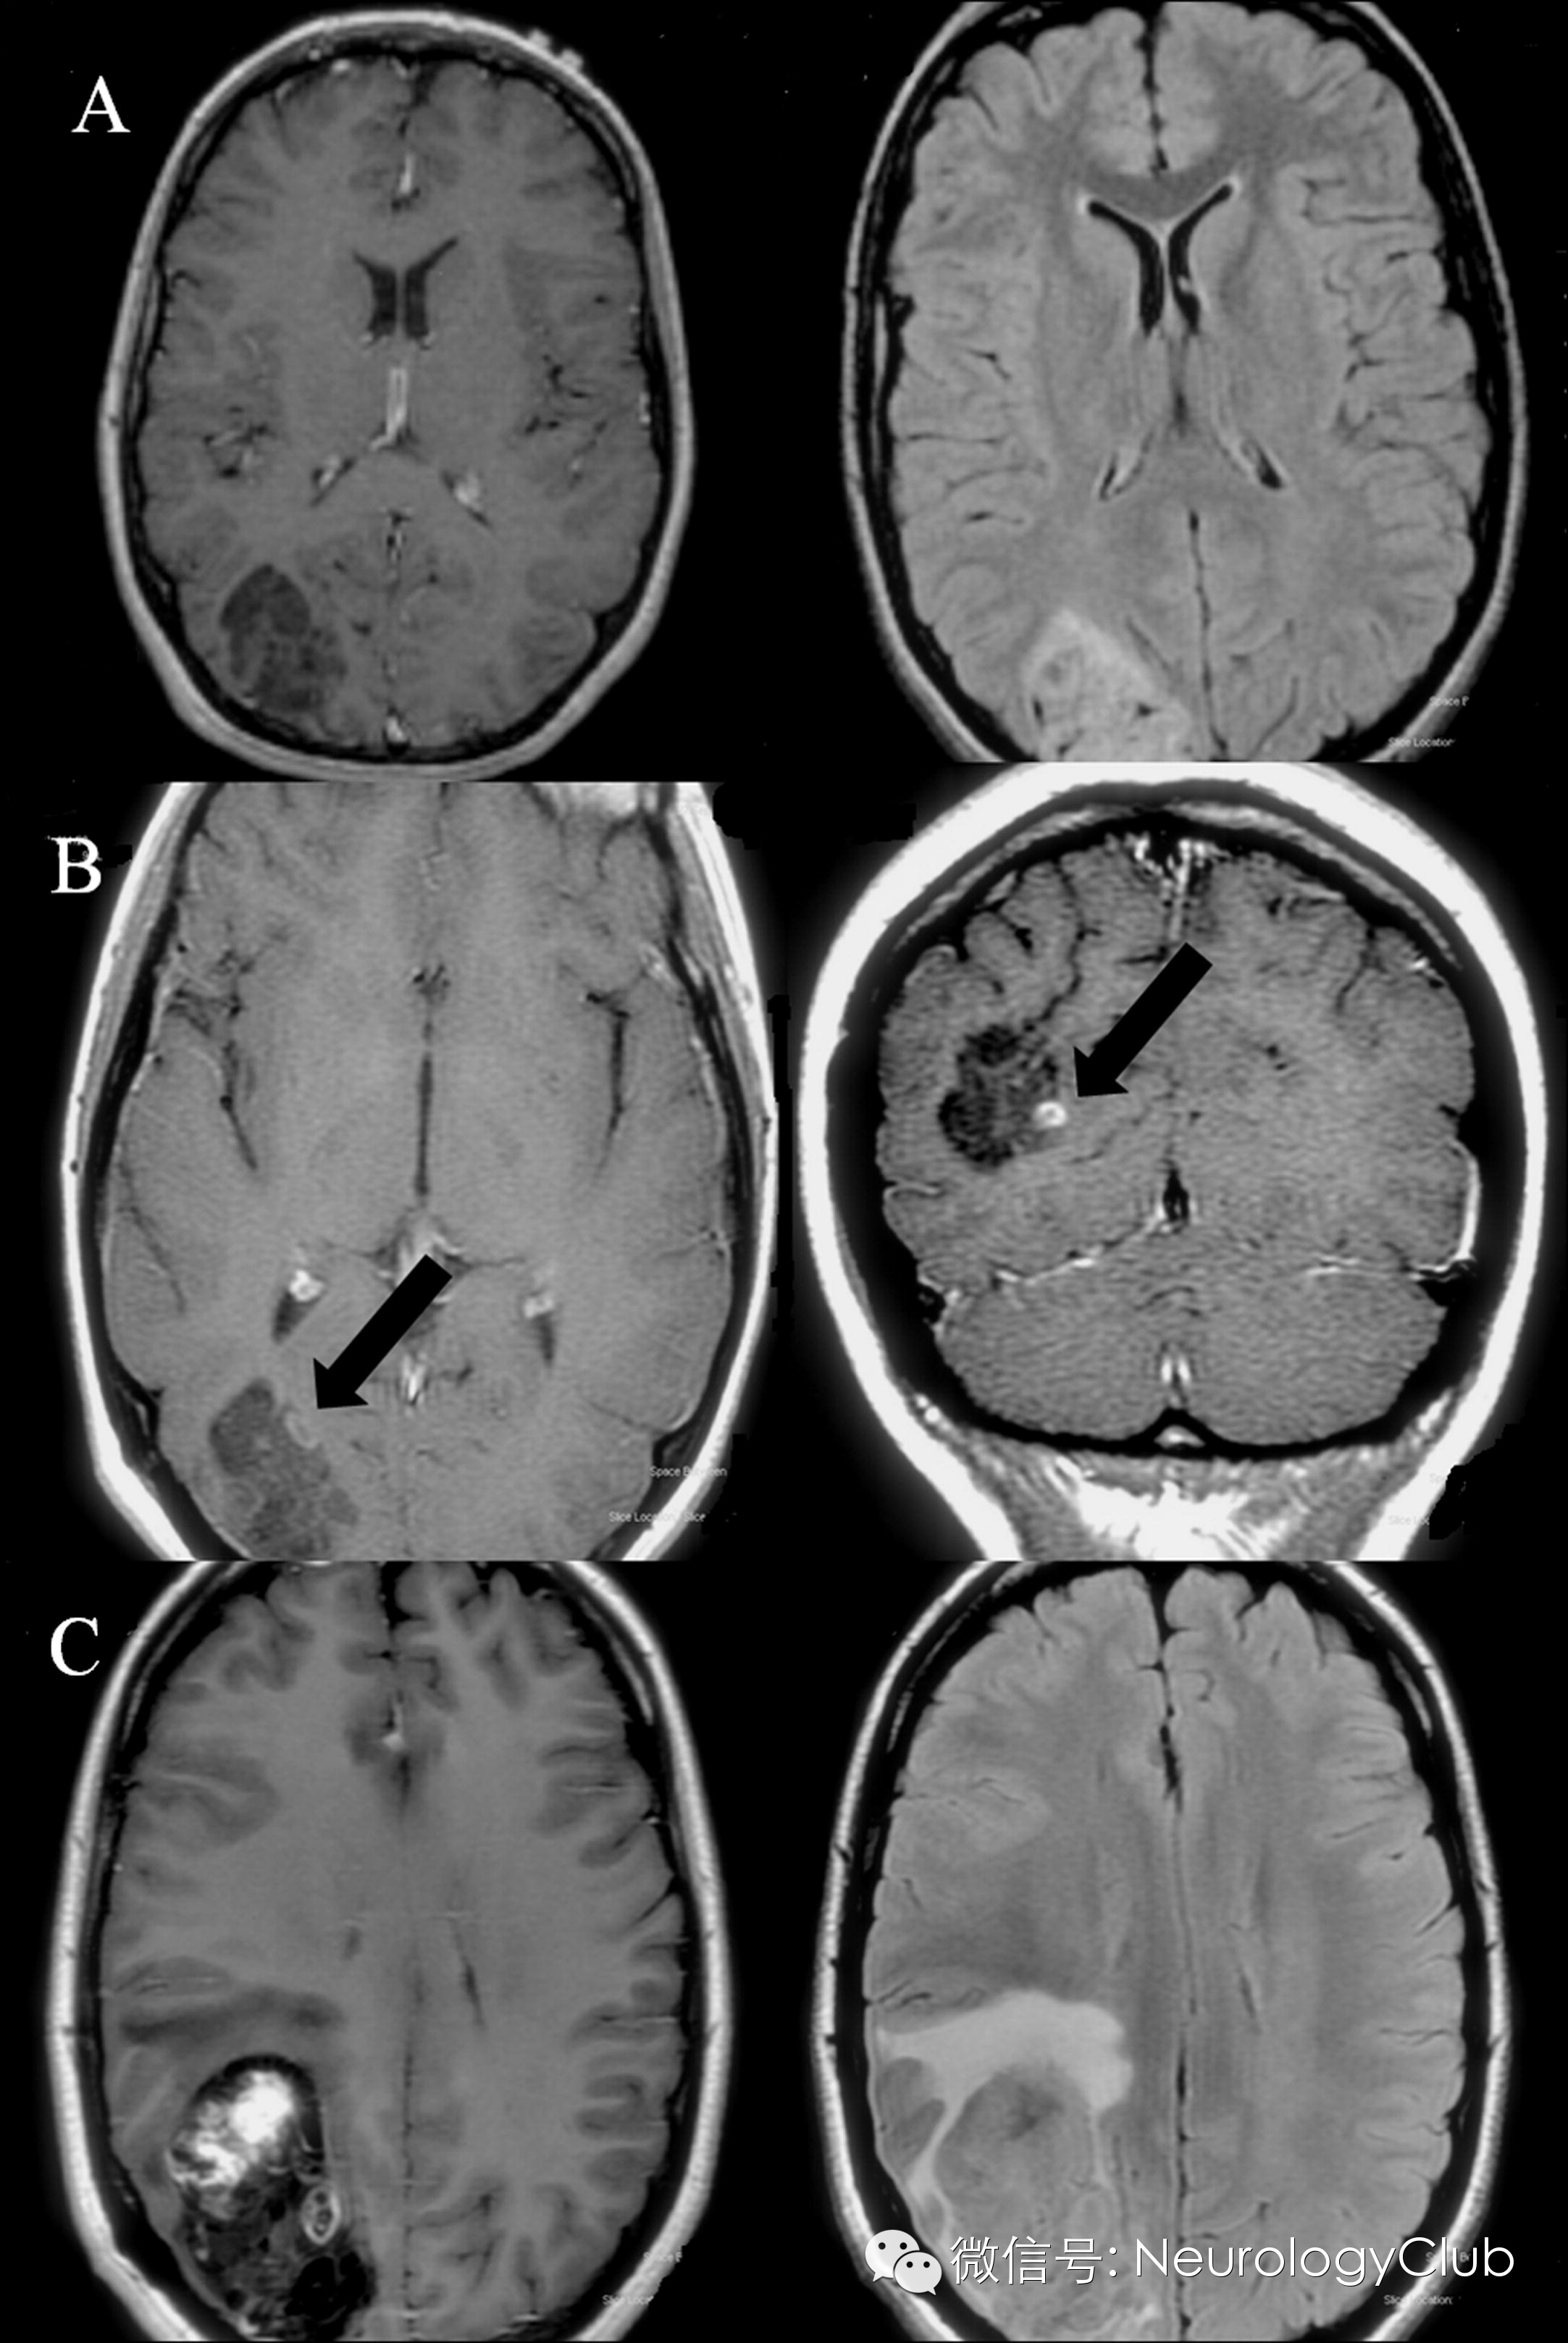

头颅MRI见右侧枕叶5.2cm大小的肿块,伴囊变和颅骨重建(图1 A)。注射对比剂后无增强,亦无占位效应。发作间期脑电图无殊。患者服用卡马西平控制发作。考虑到切除肿瘤后可能影像视力,故患者接受活检明确性质。手术中见局部脑皮质灰白伴扩张。穿刺组织病理证实为DNET,Ki67<1%(图2 A-C)。

术后患者一般情况良好,继续卡马西平治疗,仅偶尔会有视觉发作。1年后复查MRI发现肿瘤总体大小基本同前,但出现了结节样强化(图1 B)。

活检术后10年,患者因轻微脑外伤出现头痛和嗜睡,发作情况无明显改变,查体亦无视力缺损。MRI提示病灶大小进展,包括囊变部位和强化结节(图1 C)。存在占位效应和水肿。

(A:左图增强右图黑水[第一次活检前];B:增强[活检后1年];C:左图增强右图黑水[活检后10年])